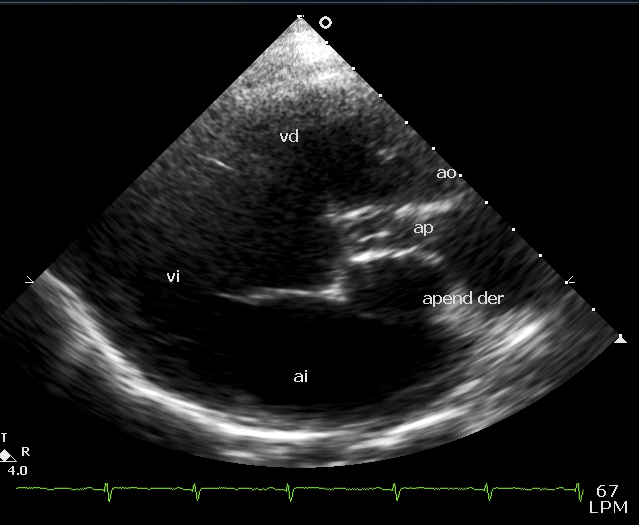

Ladie 16 yo with TGV, VSD and severe pulmonary stenosis, a vascular structure was find in palax between the posterior PA and LA In long axis with movement